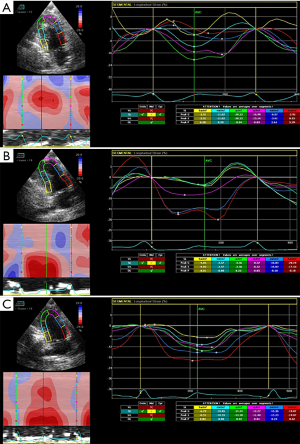

Analysis of myocardial synchrony parameters

Local systolic function indexes, Smid and SRmid, and overall synchrony parameters, LSsd and LSdif, were significantly different among the three groups (P<0.05). Contraction movement in the MI group was more asynchronous, while local contraction was enhanced and global synchronization was improved in the UTMD and UTMD-Ang1 groups (P<0.05). There were no significant differences in Sbase or SRbase among the three groups (P>0.05) (Table 2 and Figure 2).

2DSTE technology with an EchoPac clinical workstation was used for the LV systolic synchrony analysis. The boundary between the inner and outer myocardial membrane was drawn and identified according to the software. Changes in the longitudinal strain (Smid and Sbase) and strain rate (SRmid and SRbase) of the LV segment (middle segment of the anterior and anteroseptal wall) and the adjacent segment (basal segment of the anterior and anteroseptal wall) were observed to evaluate the improvement in LV local systolic function. The standard deviation of all segments’ longitudinal strain (LSsd) and the maximum difference of the longitudinal strain of all segments (LSdif) were used as indicators to assess the global systolic synchronicity.